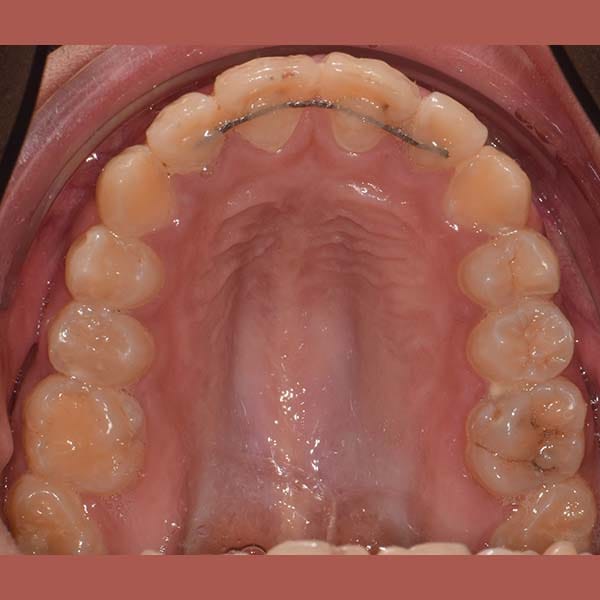

بعد شرح أن قلع الأسنان يكون ضرورياً أحياناً، وبعد الفحص الدقيق، طمأن الدكتور خالد الكاتب الأم بأنه لحسن الحظ، حالة ابنتها تسمح بالعلاج دون قلع. اعتمدت الخطة على توسيع الفكين لفتح مسافة كافية لرصف الأسنان. تم اختيار تقويم الدايمون (ذاتي الربط) لهذه المهمة، حيث يعتبر مثالياً لهذا النوع من المعالجات التي تتطلب توسيعاً فعالاً.

كما تظهر الصور، نجحت الخطة العلاجية في رصف الأسنان بشكل ممتاز وتحقيق ابتسامة جميلة ومتناسقة. وكالعادة، أصبح بإمكان صديقتنا الشابة أن تبتسم لوالدتها ولكل من حولها بثقة وسعادة.